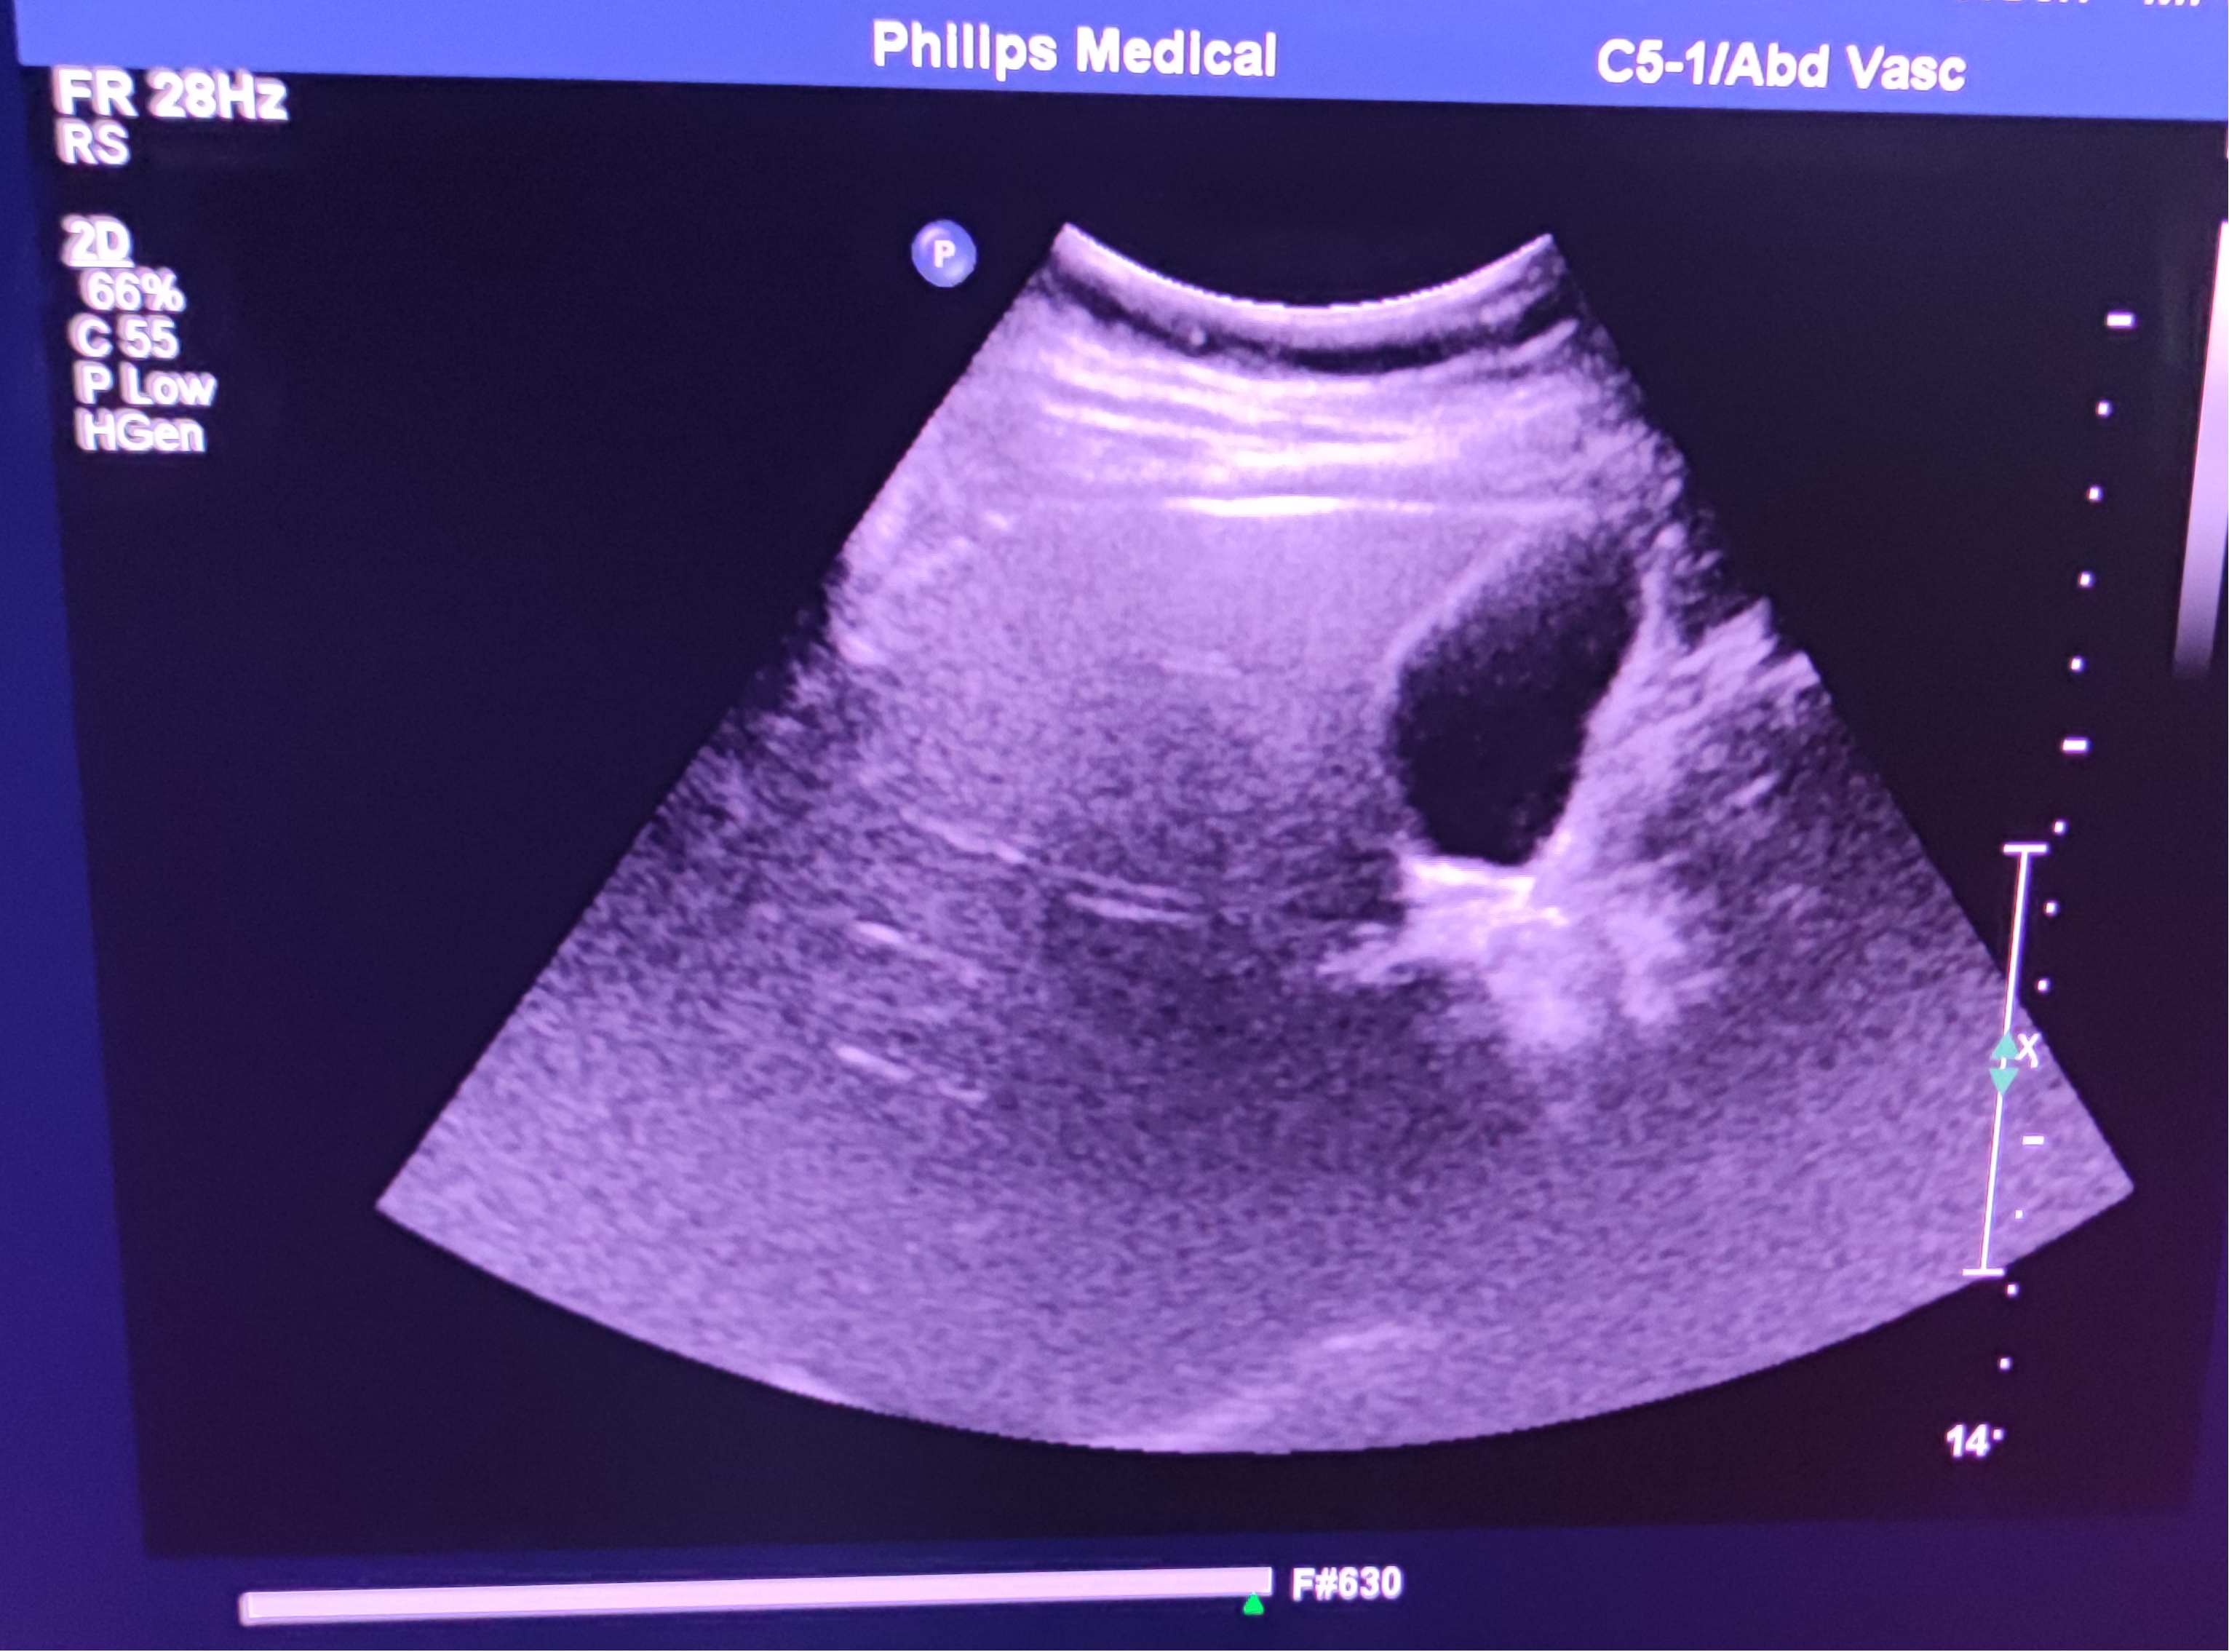

• 揭阳市慈云医院对飞利浦腹部探头C5-1故障维修进行公开市场调研,欢迎符合资格条件的供应商报名参与,项目内容如下:

设备名称

品牌

型号

故障情况

腹部探头

飞利浦

C5-1

成像部分区域显示模糊。如下图